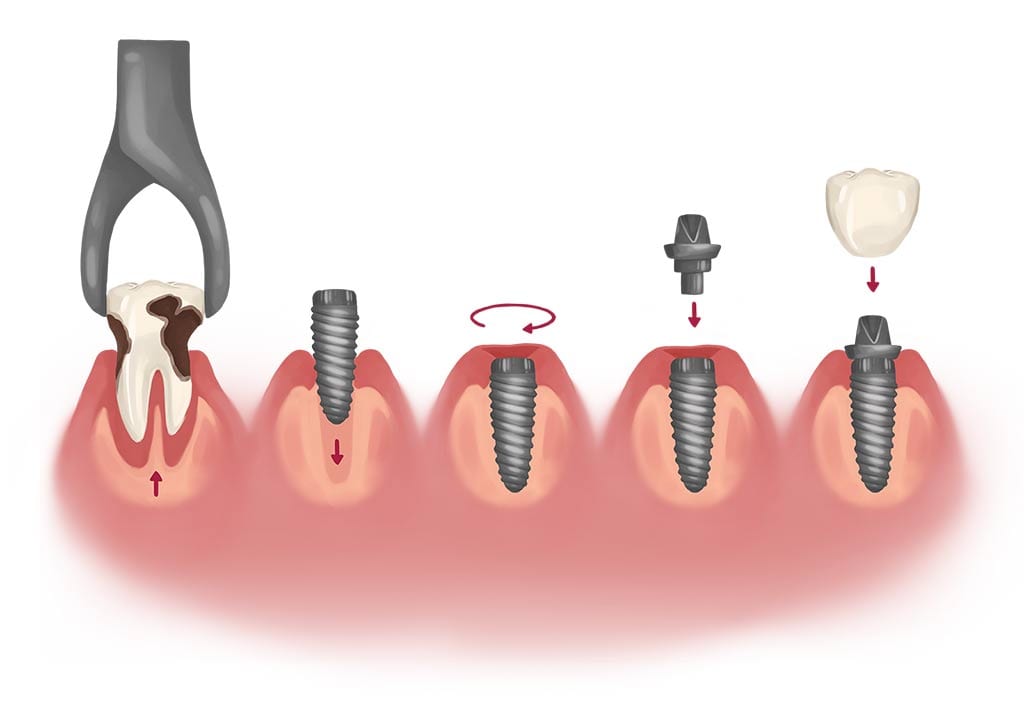

The process of receiving dental implants

Your dentist will run you through the treatment options available to you. But keep in mind that receiving dental implants is a two-step process that takes time to complete. This is not something you can rush through quickly.

The first step is receiving your bone graft, in order to give the implants a healthy foundation to settle into. After your bone grafting is done, you will need between 4 and 5 months to heal. This does depend on the type of bone graft.

Once you are healed, your second step is to receive the dental implants. Again, healing takes time, and you will need to follow aftercare protocol. Having the dental implants put in is a surgical procedure, so some self-care and rest in the days after is important.

Expect to be on a diet of soft food for at least 24 hours. Swelling and post-surgery discomfort is likely to be present for up to 4 days.